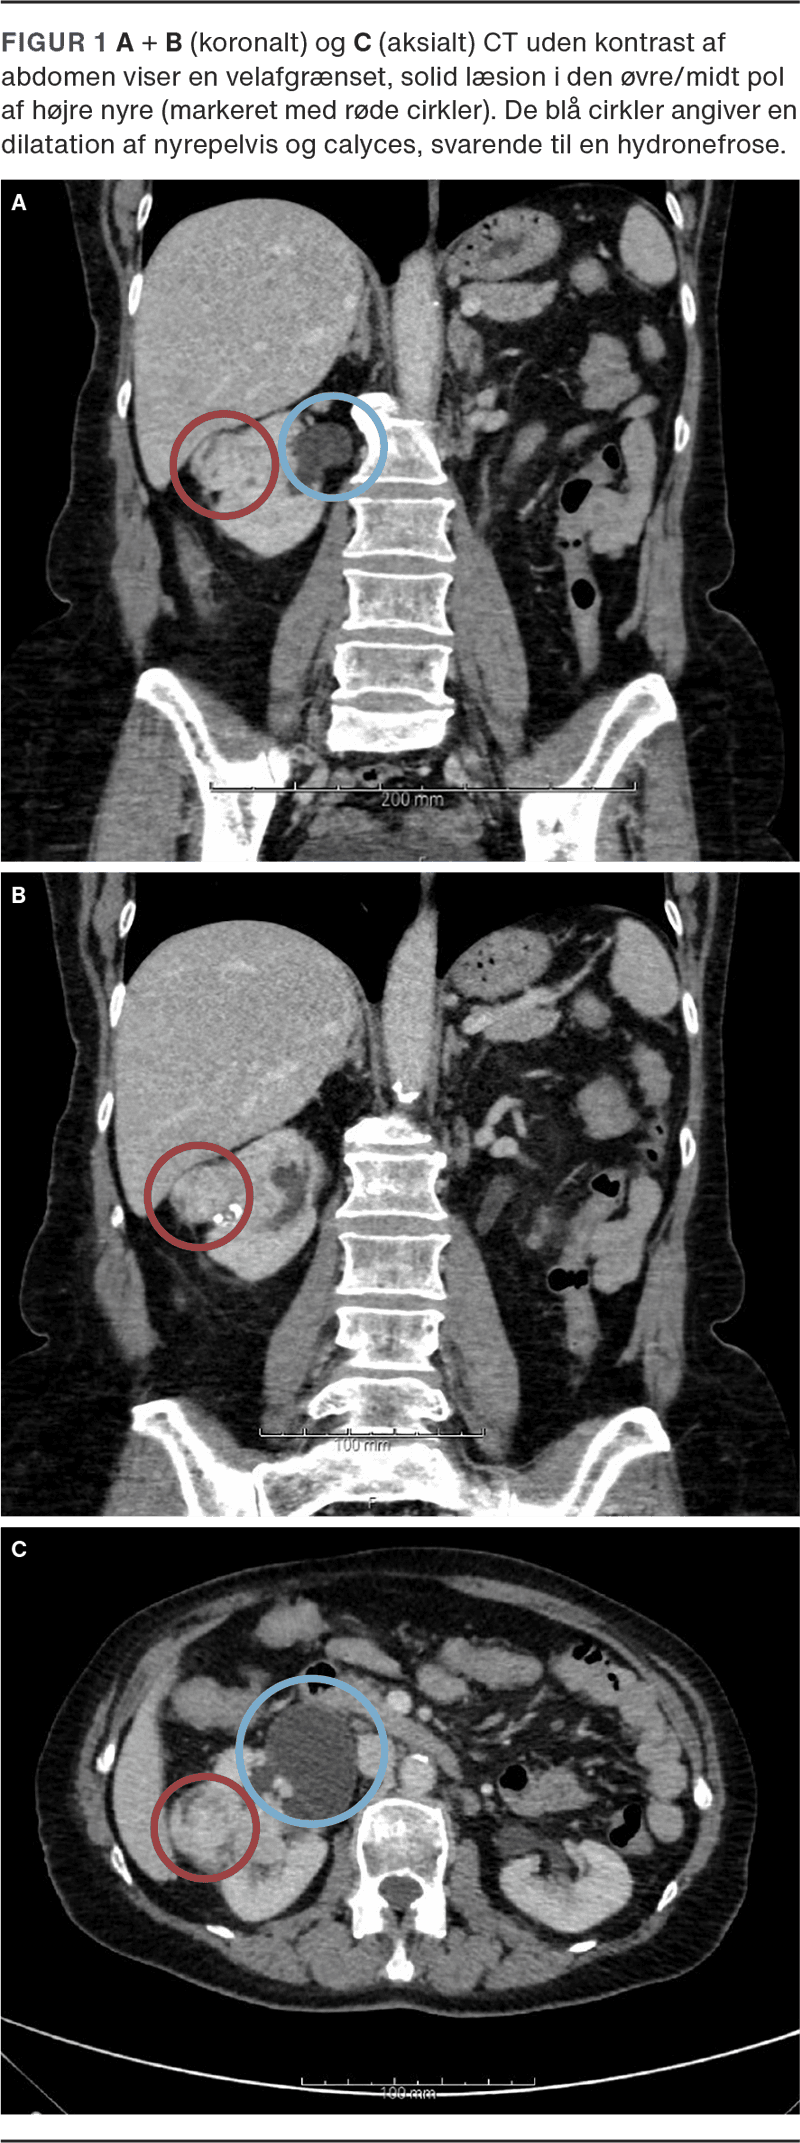

En CT af thorax, abdomen og bækken påviste en tumor på 5 × 3,5 cm i højre nyre. Derudover blev der fundet parenkymal forkalkning og hydronefrose i højre nyre, formentlig på grund af en udiagnosticeret ureteropelvin stenose. Patienten gennemgik radikal højresidig nefrektomi. Histologisk undersøgelse viste clear cell renalcellekarcinom (ccRCC), stadie pT3a, og Leibovich-score 5 (Figur 1).